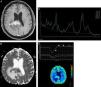

Distinguishing between PCNSL and infectious brain lesions is difficult but clinically relevant, particularly in immunocompromised patients. In this setting, nonconventional MRI may be used to differentiate focal brain lesions in PCNSL from neurotoxoplasmosis, cryptococcosis, tuberculosis and intracranial abscesses.21 DWI with ADC maps is useful to distinguish between toxoplasmosis and PCNSL. Early toxoplasmosis may be associated with areas of restricted diffusion on DWI; however, toxoplasmosis lesions have significantly greater diffusion than in PCNSL. ADC ratios that ranged from 1.0 to 1.6 have been reported for both PCNSL and toxoplasmosis, whereas ADC ratios greater than 1.6 were associated solely with toxoplasmosis.13 In addition, toxoplasmosis may be indicated by the presence of Lip and Lac and a decrease in the NAA/Cr ratio on MRS. Conversely, markedly elevated Cho levels would favor a PCNSL diagnosis.4,11 The accuracy of MRS is inversely proportional to the extension of necrosis (Figure 3).

A focal brain lesion in an AIDS patient (toxoplasmosis versus lymphoma). An axial T1 image after intravenous gadolinium administration (A) shows a large periventricular lesion in the left thalamus with extensive necrosis (asterisk) and thick peripheral enhancement. An axial apparent diffusion coefficient map (B) confirmed a very low signal intensity in the solid portion of the lesion (arrowheads) compared with the central area of necrosis (asterisk). Additionally, note the hyperintensity of the perilesional vasogenic edema. Proton magnetic resonance spectroscopy (C) confirmed the presence of elevated lipid and lactate (0.9–1.3ppm) and choline levels with reduced N-acetylaspartate levels. A magnetic resonance perfusion sequence (dynamic susceptibility contrast magnetic resonance image T2*) (D) confirmed the absence of neoangiogenesis (low relative cerebral blood volume). These features supported the diagnosis of lymphoma.

A non-enhancing presentation of PCNSL was found in 1% of patients in a large series of immunocompetent patients and was documented in immunocompromised patients.21,30,31 ‘Lymphomatosis cerebri’ is frequently misdiagnosed as diffuse nonspecific leukoencephalopathy, Binswanger's disease (subcortical ischemic vascular dementia), infectious encephalomyelitis including progressive multifocal leukoencephalopathy, toxic or metabolic abnormalities, unknown autoimmune diseases, or neoplasms such as gliomatosis cerebri.9,32–35 DWI and MRS may support a presumptive diagnosis of brain infiltrative neoplasia; however, an accurate diagnosis is only possible after a brain biopsy.36 MRS may show increased Cho levels and Cho ratios (Cho/NAA>1.9), which suggest infiltrative neoplastic disease (Figure 6).35 DWI is variable and can depict heterogeneous areas with restricted water molecule movement. Perfusion MRI techniques are not helpful because the rCBV is not increased and there is no abnormal permeability of the BBB.

Lymphomatosis cerebri in an immunocompetent patient. An axial fluid-attenuated inversion recovery image (A) shows unspecific diffuse hyperintense areas on both brain hemispheres that cross the splenium of the corpus callosum with no mass effect. No contrast enhancement was observed (not shown). A comparative fluid-attenuated inversion recovery image (B) was obtained after two months without specific therapy confirming the extensive progression of the disease, and exhibiting confluent hyperintensity of both brain hemispheres, predominantly of the left. Minimal mass effect and no gadolinium-enhanced areas were observed. A proton magnetic resonance spectroscopy study (C) was useful to support a presumptive diagnosis and demonstrated increased choline levels and an increased choline/N-acetylaspartate ratio (>1.9), which were associated with reduced N-acetylaspartate levels and elevated lactate peaks.